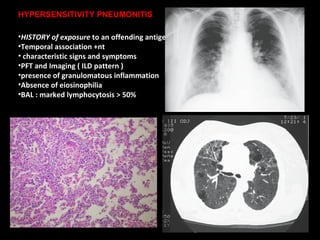

HISTORY of exposure  to an offending antigen Temporal association +nt characteristic signs and symptoms PFT and Imaging ( ILD pattern ) presence of granulomatous inflammation Absence of eiosinophilia BAL : marked lymphocytosis > 50% HYPERSENSITIVITY PNEUMONITIS